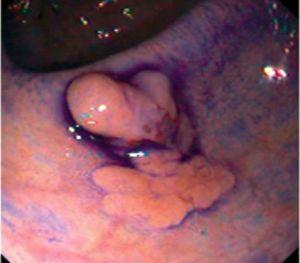

Fig. 3. Examples of flat lesions with conventional examination and after the application of indigo carmine 0.2-0.5%. a, b) Small flat adenoma, 3 mm in size. c, d) Large flat adenoma, 15 mm in size. e, f) Completely flat lesion (IIb in the Japanese classification). g, h) Depressed lesion, 3 mm in size) (IIc in the Japanese classification). I, J) Depressed lesion, 7 mm in size, histopathological study revealed submucosally invasive cancer (traditionally IIc in the Japanese classification, although recently such depressed lesions with a distinct central protrusion indicating submucosal invasion are termed IIc + Is). k, l) Flat elevated lesion with central depression, 10 mm in size, corresponding to a submucosally invasive cancer (IIa + IIc in the Japanese classification).

Fig. 4. Examples of protruding lesions with conventional examination and after the application of indigo carmine 0.2-0.5%. a, b) Sessile polyp. c, d) Subpedunculated polyp. e, f) Pedunculated polyp. g, h) Submucosal lesion (indigo carmine shows distinct innominate grooves, ruling out an epithelial lesion). i) Subpedunculated polyp. j) After indigo carmine application, a flat elevated lesion similar in size to the protruding segment is clarified.